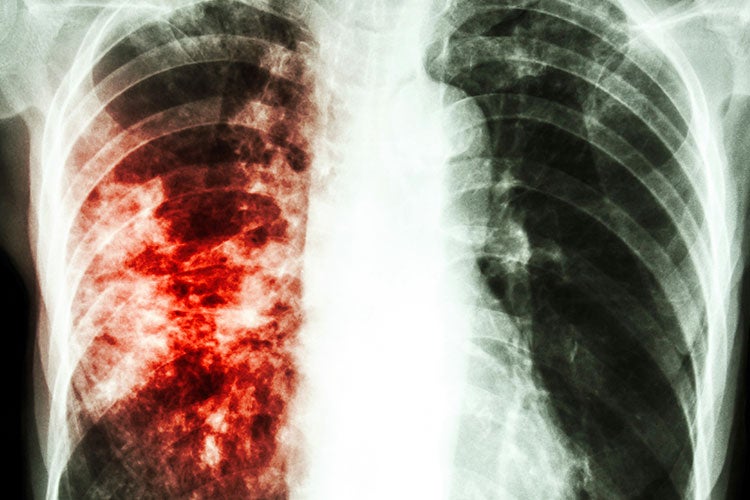

Медицинская тема: легочные осложнения при пневмонии